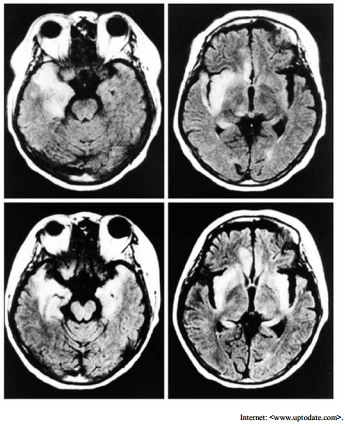

Um paciente com vinte e cinco anos de idade foi admitido em um hospital apresentando, havia cinco dias, febre persistente, cefaleia holocraniana, oscilações de humor e alterações no seu comportamento habitual. O paciente fez uso de analgésicos e antitérmicos, em casa, administrados pela própria família, mas a resposta aos medicamentos foi parcial e temporária. No quinto dia, o paciente estava excessivamente sonolento, e apresentou crise convulsiva tônico-clônica, sendo então levado para atendimento médico de urgência. Acerca desse caso clínico, julgue o item a seguir considerando o exame de imagem mostrado. O agente etiológico da infecção é do mesmo tipo que causa a meningite linfocítica recorrente, também conhecida com meningite recorrente de Mollaret.